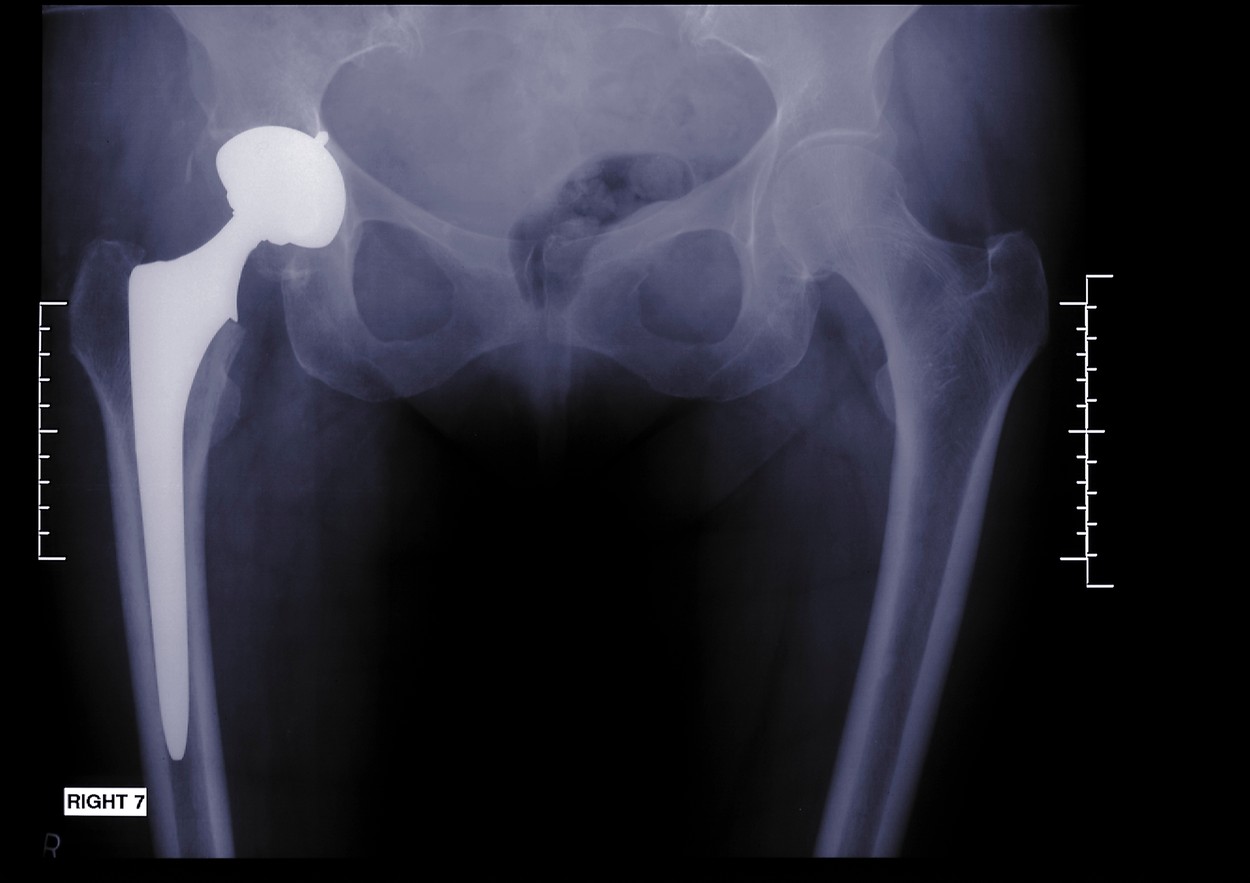

Zlom kolka je za starega človeka pogosto celo smrtna obsodba. Kar približno četrtina jih umre v prvem letu po poškodbi. "Poškodba, ki zahteva operativni poseg in bolnišnično zdravljenje, pri starejših pogosto dokončno poruši krhko ravnovesje in organizem se nikoli več ne pobere," pravi dr. Anže Kristan.

Dodatna komplikacija pri zlomih pri starejših je v tem, da jih ima veliko že vstavljeno kakšno "endoprotezo", ali umetni kolk ali koleno. "Padec lahko hitro povzroči t. i. obprotezni zlom, ki je zelo zahteven za zdravljenje."